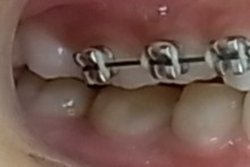

外傷症例には早期に矯正装置(ブラケット)を装着していきます。

そのことで保定効果を期待します。また、外傷によって変わってしまった歯の位置を元に戻すことが出来るからです。

その後、下顎にも矯正装置を装着して歯並びを綺麗にしていきます。

その後、MEAW(マルチループ)と顎間ゴムを24時間利用する事で受け口(下顎前突)と歯並びを改善していきます。